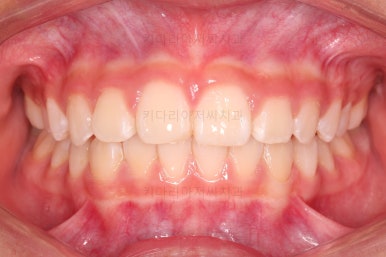

부산소아교정 마무리 사진입니다.

프리올소로 유지과정까지 총 2년 3개월 가량 걸렸고요.

이정도 마무리면 굳이 2차교정까지 안해도 되겠죠?

정교한 조절은 안했지만 치열이나 교합/맞물림 등 매우 좋아졌습니다.